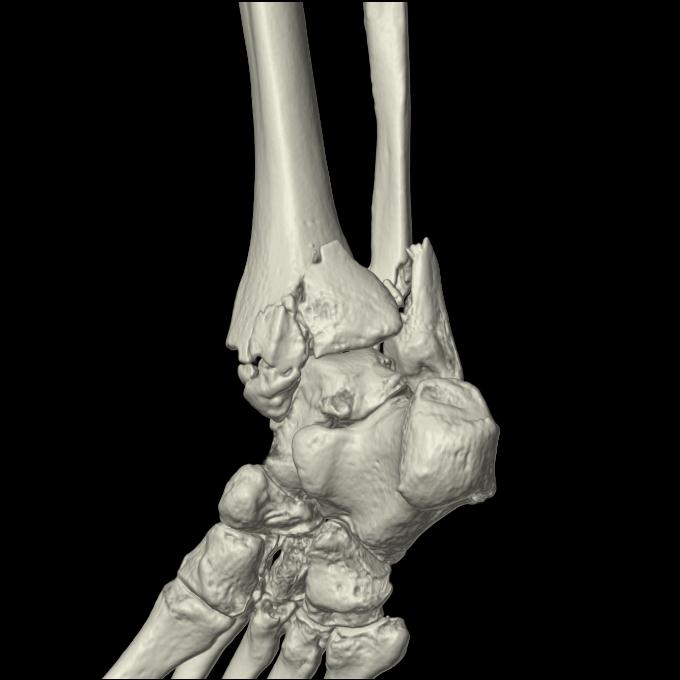

102755 1/4 2R 1/15 2R 右足関節 68歳女性 右三果脱臼骨折